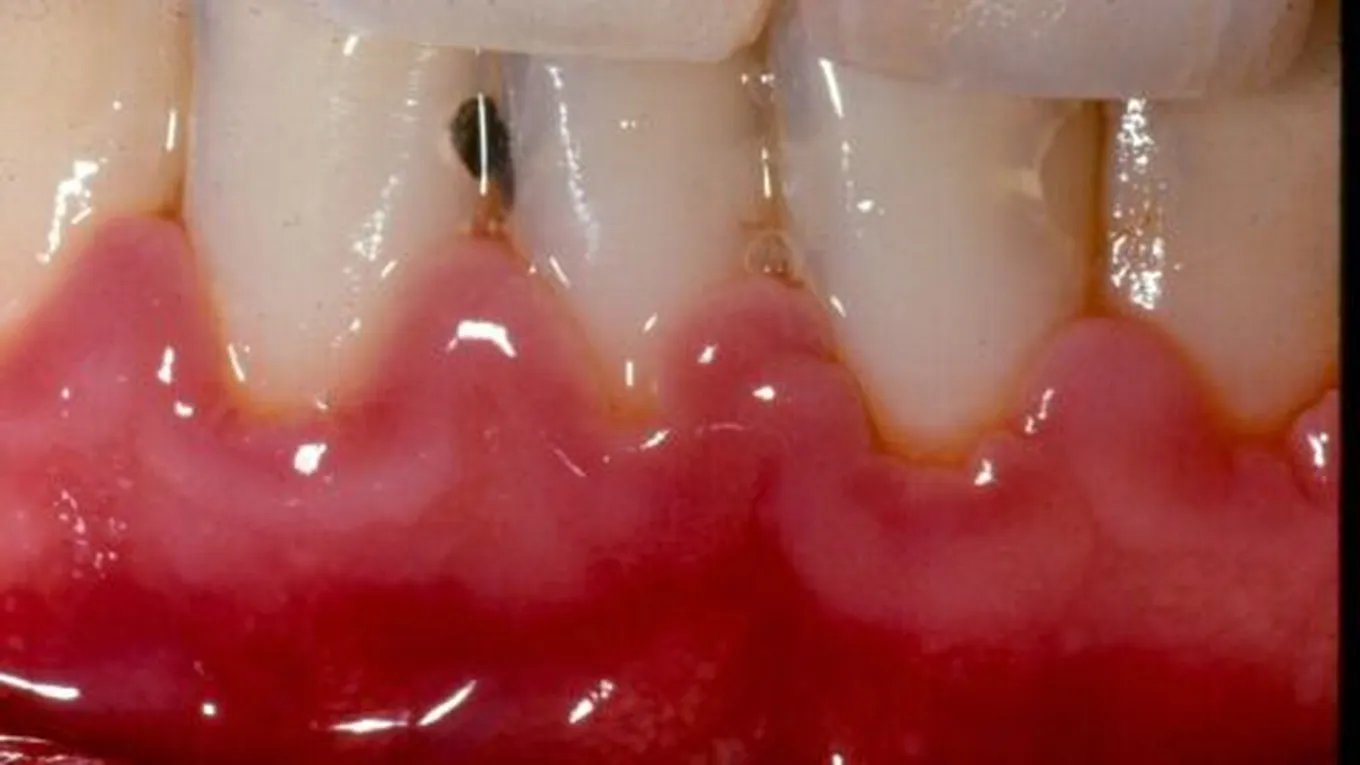

- نزول الدّم من اللثة عند تنظيف الأسنان بالفرشاة والمعجون، وأحياناً قد تنزف اللثة دون سبب.

- حدوث التورّم والانتفاخ في اللثة.

- تغيّر لون اللثة إلى الأحمر القاني.